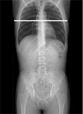

スロットラジオグラフィー(長尺撮影)について

『スロットスキャン』による長尺撮影は、移動しながらほぼ垂直なX線を照射するので歪みが少なく、つなぎ目をなくしたスムーズな全脊椎や全下肢の画像を得ることが可能です。

FPDを搭載しているので従来の全脊椎、全下肢の撮影に比べ、2分の1~10分の1の低線量で撮影することが可能です。

透視台を動かすことで全脊椎、全下肢、全上肢の撮影において、立位・臥位で容易に撮影することが可能です。